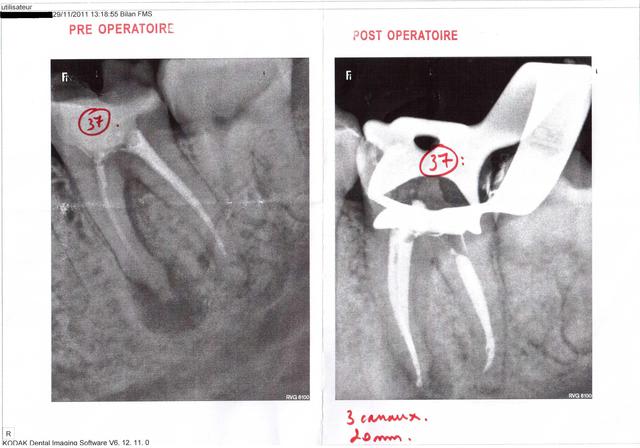

Voici les radios de l'endo exclusif. A noter la racine distale qui avait été retraitée par sa dentiste quelques semaines auparavant (la racine mésiale n'ayant pas été retraitée car elle proposait une hémisection).

J'ai éclairci l'histoire de la "deuxième couronne à 200€", car j'avais vraiment du mal à y croire ... j'ai épluché les devis, et en fait mon copain a compris que l'inlay-core à 220€ était sa prochaine couronne provisoire :D